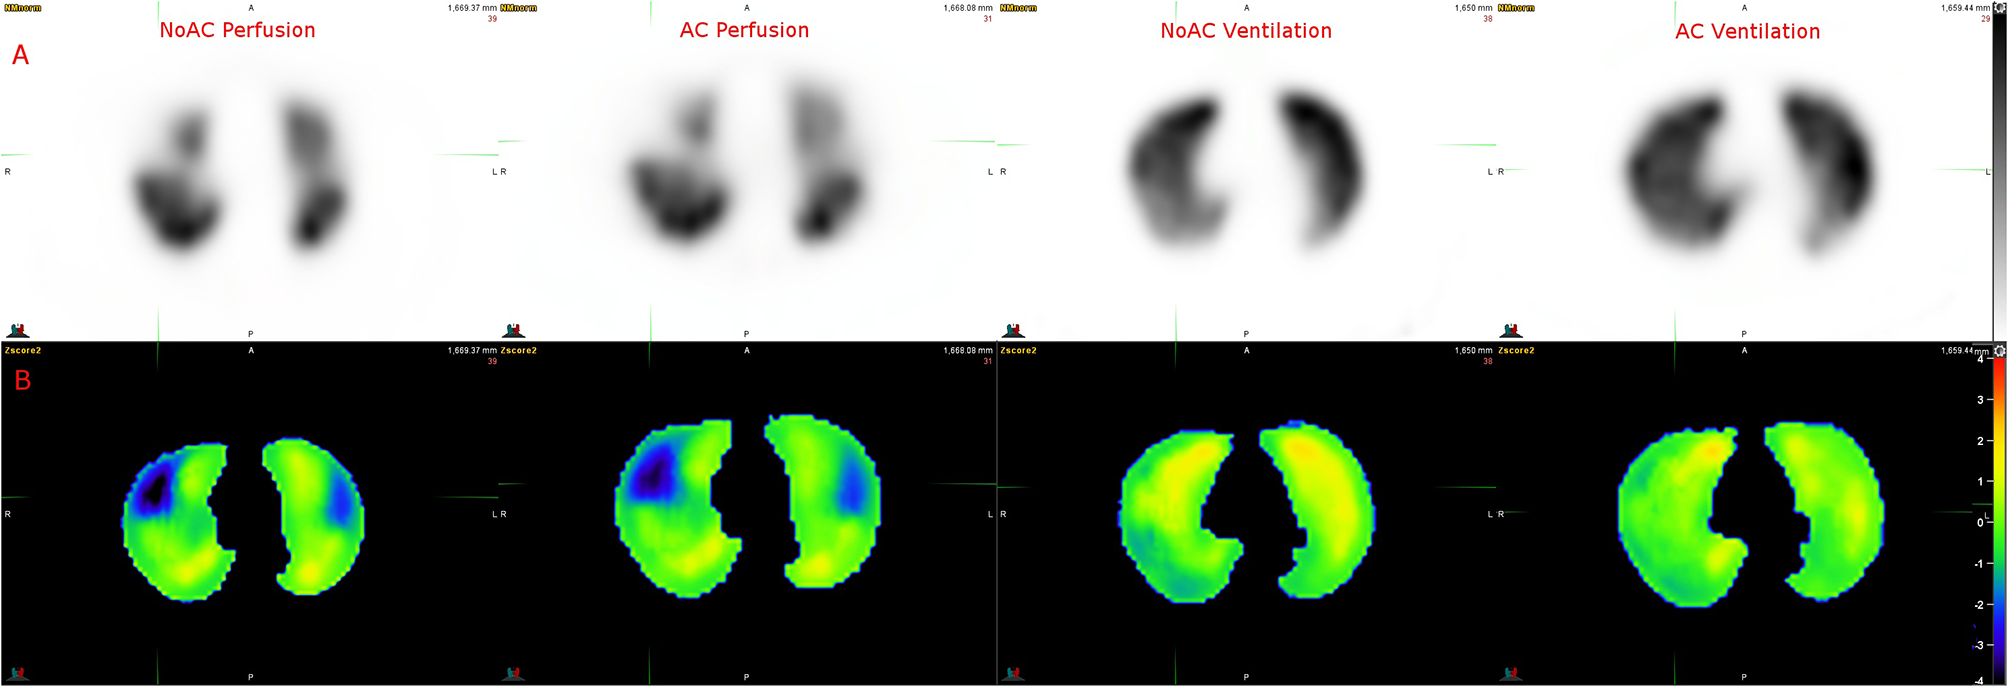

Figure 5 shows the Z-score maps calculated using a V/Q SPECT/CT scan with acute PE. Ventilation Z-score map did not show significant variation, consistent with visual interpretation. Perfusion Z-score map showed clear low Z-score areas (<−1 SD) in the pulmonary regions with PE.

Figure 5

Example of Z score analysis. (A) Axial slices of NoAC Perfusion, AC Perfusion, NoAC Ventilation and AC Ventilation. (B) The corresponding generated Z-score maps.

Our results illustrate the complexity of delineating regional lung function on SPECT imaging. Lung V/Q SPECT segmentation is not trivial because of regional variability associated with the low spatial resolution. Multiple methods have been proposed like thresholds methods, local threshold methods, histogram-based threshold methods, but all have difficulties to deal with physiological heterogeneity (3, 33, 34). A Z-score based method (Z-score threshold) could help to discriminate normal and abnormal uptakes, taking into account statistical variability, as shown in Figure 5.